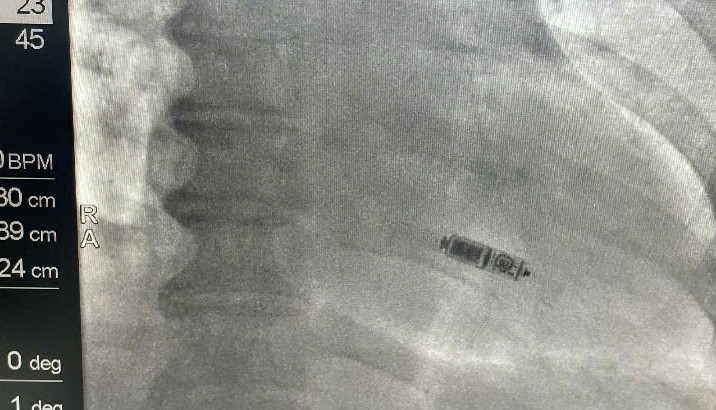

O procedimento foi realizado pelo Dr. Nguyen Quoc Khoa e pela equipe de implante de marca-passo do Hospital 30-4, sob o apoio direto do Dr. Vo Thanh Nhan, Diretor do Centro de Cardiologia Intervencionista do Hospital Tam Anh, na Cidade de Ho Chi Minh. A equipe implantou o dispositivo através da veia femoral utilizando um cateter, posicionando-o com alta precisão na câmara cardíaca. A intervenção transcorreu sem intercorrências e o dispositivo funcionou de forma estável imediatamente após o procedimento.